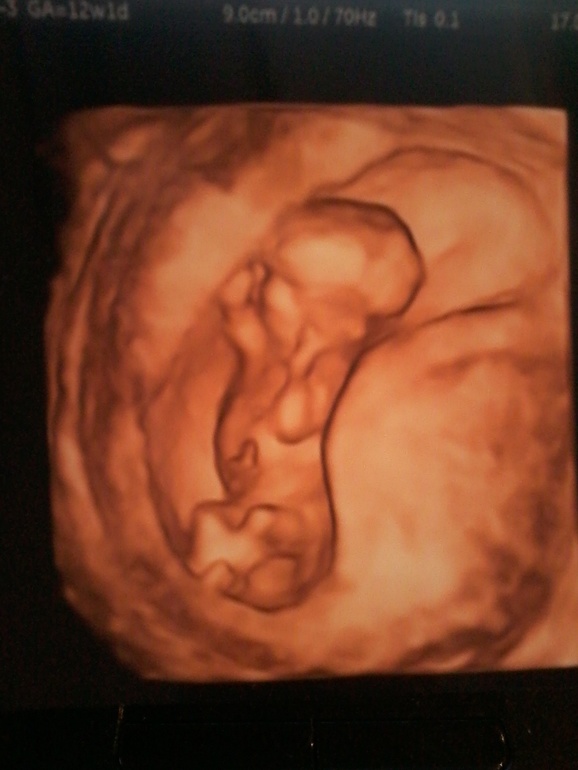

Результаты: УЗИ, КТГ, доплера, скринингаПрошли сегодня первый скрининг. Врач ну очень хорошая, все рассказала и показала все до пальчиков и ушек ))) Ходили с мужем и дочкой, все под приятным впечатлением... У малыша все сформировано, все отлично. Смотреть очень умиляет, до слез ) На 95% сказали что МАЛЬЧИК )))

Очень рада за вас! У нас вчера было 12+1 и мы тоже это прошли))) это у вас 3д фото такое интересное? Наш малыш тоже за головку держался, и тоже парня обещали нам )))

Да 3D, не особо четко фото, сливаются маленькие части (пальчики например и скрещенные ножки), но в живую это смотрелось очень здорово. Долго смотрели как он бегает, вытягивался в полный рост и реально бегал, очень мило ))))